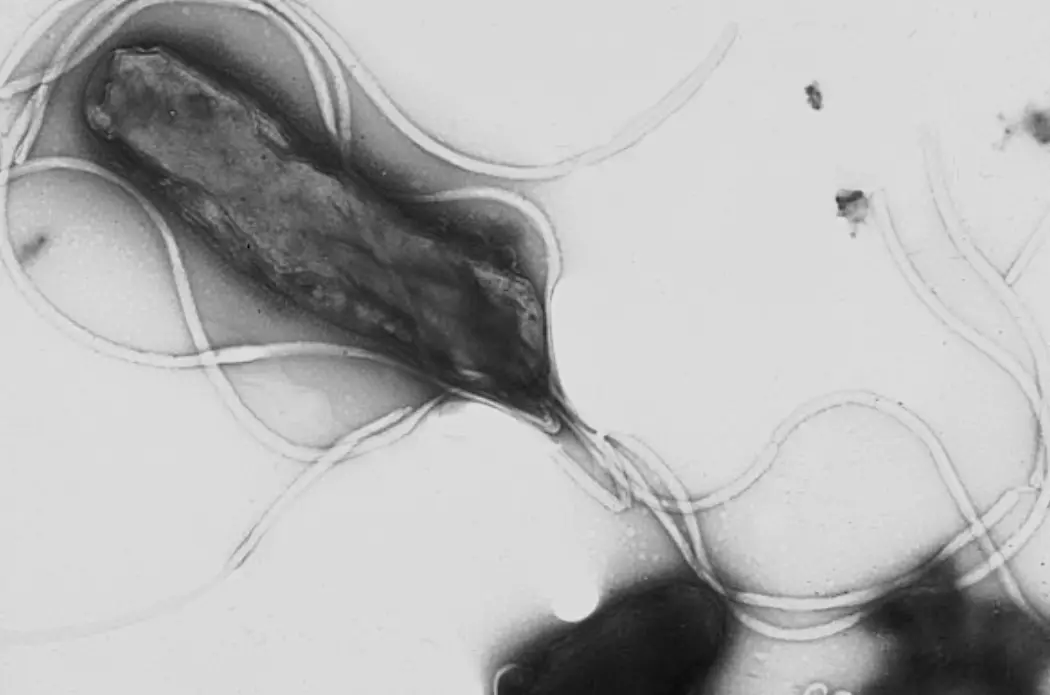

ئاشقازان چىقىش ئېغىزى بۇرمىسىمان تاياقچە باكتېرىيەسى ئادەم بەدىنىدىكى ئىنتايىن كۈچلۈك كىسلاتالىق مۇھىت بولغان ئاشقازان سۇيۇقلۇقىدا ياشىيالايدىغان بىردىنبىر باكتېرىيە ھېسابلىنىدۇ. ئۇ ئۆزىدىن ئۇريازا ئېنزىمى چىقىرىپ، ئەتراپىدا نېيتراللاشتۇرغۇچى بىر قەۋەت پەيدا قىلىدۇ ۋە ئاشقازان شىللىق پەردىسىگە بېرىپ يۆگىشىۋالىدۇ. يېقىنقى يىللاردىن بۇيان تىببىي ساھەدە بۇ باكتېرىيەنى كونترول قىلىش جەھەتتە زور ئىلگىرىلەشلەر بولدى.